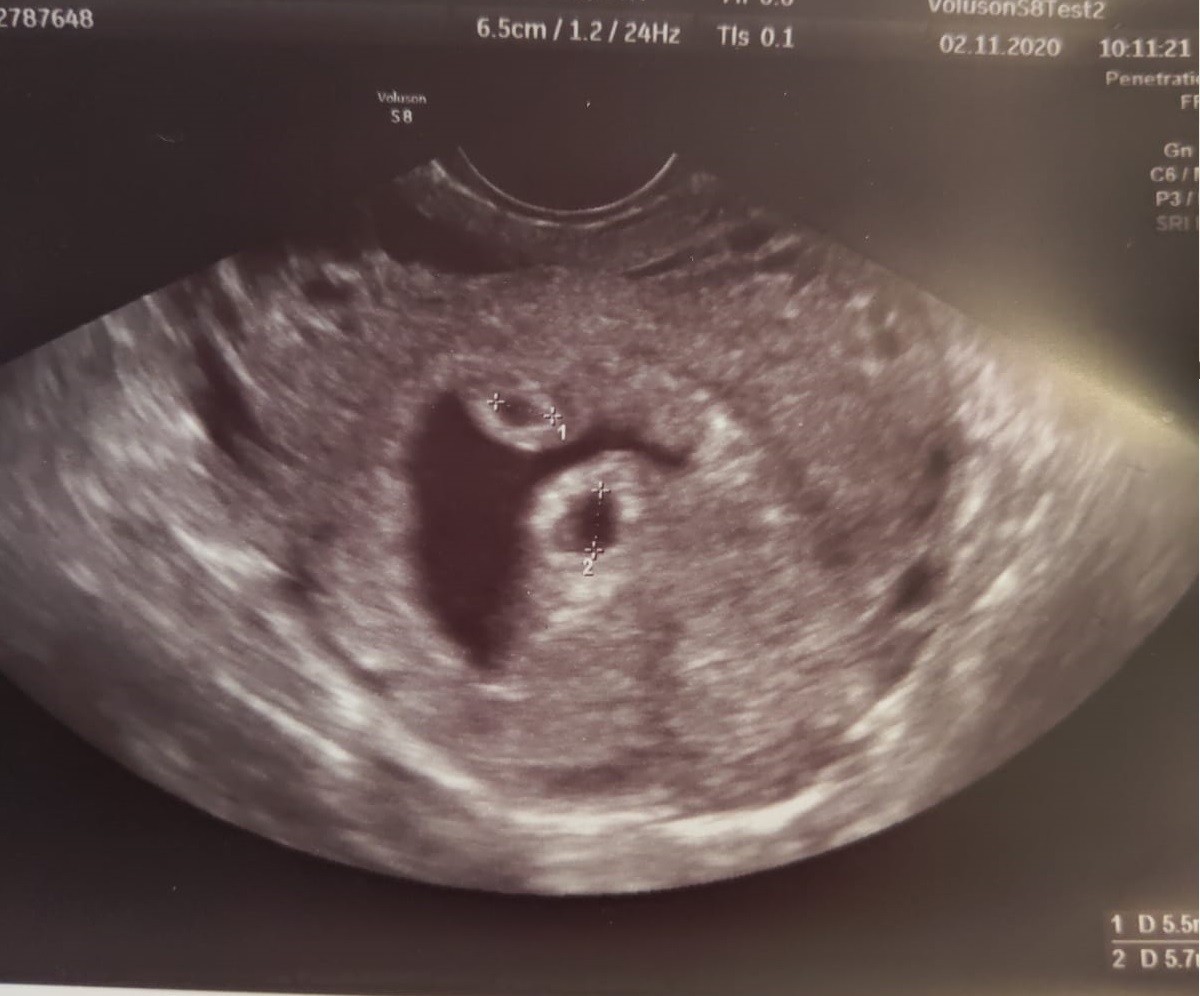

No wiec dobra jest taka, że widać dwa pecherzyki ❤❤, które są troszke mniejsze niż powinny - bo 5 tydz 2 dzień a według zapłodnienia komórek powinien być 5 tydz 5 dzień, ale to szczegół, wiem, ze miałam późno implantację, dopiero 4-5 dni po transferze 5 dniowych blastek, wiec moze to normalne ze są mniejsze. Bardziej martwi mnie fakt, że ta ciemna przestrzeń to krwiak. Nie chcę czytac w necie na ten temat, bo wiem, że spanikuję, wiec czekam na telefon od mojego lekarza i zobaczymy co on powie. Bo w czasach covidowych u mnie rano robią badania i USG a lekarz dzwoni później.

Dziewczyny jeśli miałyście krwiaka w ciąży napiszcie jak to było, czy sam Wam sie wchłonął czy zaczęłyscie krwawic. Ehh... nie można ciaży po in vitro przeżyć w spokoju